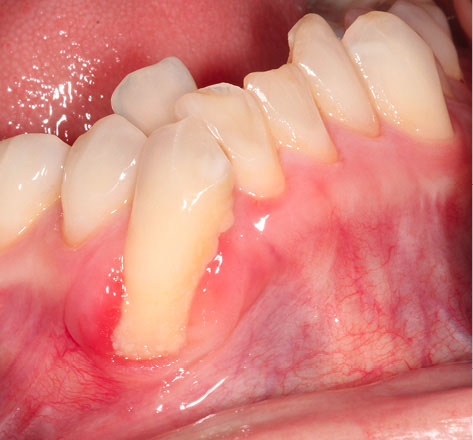

Figure 2 shows the final tunnel preparation before the placement of CTG. Figure 3 shows the harvested CTG positioned on the exposed root surface to check its dimensions before placement inside the tunnel on the buccal aspect of tooth #43. Figure 4 shows suturing after the CTG has been positioned inside the tunnel. Please note that the sutures were kept longer than usual to prevent the poking of the suture ends into the lower lip and buccal mucosa. Figure 5 shows the postoperative condition at five-week interval.

japid-12-90-g003

Figure 3. The harvested CTG positioned on the exposed root surface to check its dimensions prior to placement inside the tunnel on the buccal aspect of tooth 43.